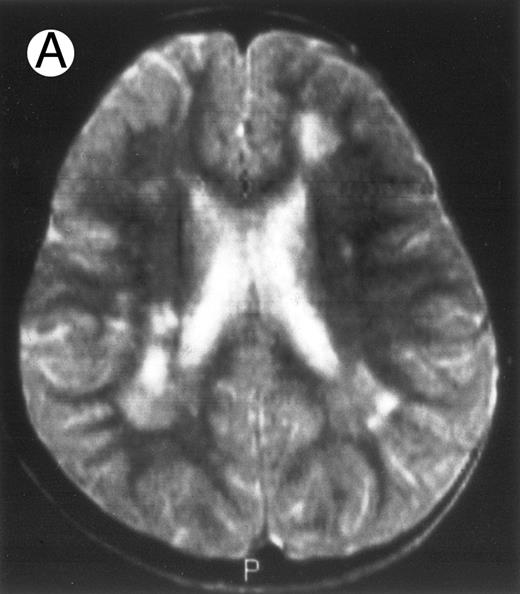

Evolution of brain lesions during HLH. (A) MRI of a 41/2-year-old girl showing focal white matter hypersignal on T2-weighted images. (B) MRI of the same child 1 year later with an important atrophy of both the white matter and the cortices.

Together, 19 patients had primary severe CNS disease progression or CNS relapse (Fig 1). Three of 19 had a CNS relapse characterized by meningitis only. Neurological symptoms occurred in 16 of these 19 patients (9 from the onset and 7 after the initial meningitis) (Fig 1). No clinical or neuroradiological difference was detected between the patients who developed neurological symptoms as the initial CNS manifestation or after initial meningitis (Table 1). The occurrence of these neurological manifestations marked a turning point in the evolution of the disease, as chemotherapy led to an improvement of the neurological symptoms in only three patients despite the use of intensive treatment by MTX IT. In these three patients, neurological sequelae persisted after the first symptoms and a relapse occurred within 3 to 10 months. Brain imaging was repeated during chemotherapy for four patients with progression of the CNS disease: in three patients, a severe brain atrophy developed (Fig 3A and B) and in the last patient who initially had contrast enhancement in cerebellar white matter, a cerebellum parenchymal loss was observed (Fig 2C). All of these 19 patients treated by chemotherapy only (n = 15) died during a last episode of coma and brain stem symptoms associated with a systemic hemophagocytic syndrome, 6 ± 6 months after the first neurological symptom (irrespective of the age at this first event). Four of these 19 patients were transplanted (one patient received an HLA-identical BMT, three an HLA-partially identical BMT). Median delay between diagnosis and BMT was 14 months (range, 2 to 20 months). All of these four patients died of BMT-related toxicity and/or disease progression.